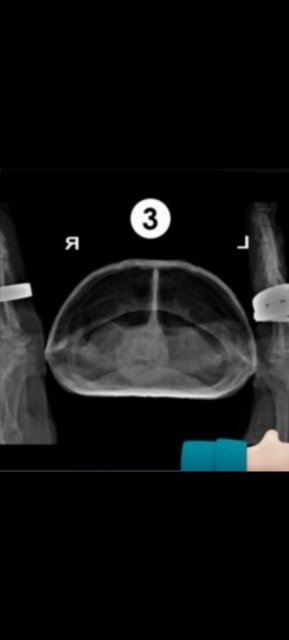

Консультанты moth Ваше имя: Мария Локация: Москва Опубликовано: 26 марта 2024 Консультанты Опубликовано: 26 марта 2024 @Владимир* если будете делать рентген, то нужны проекции 1 и любая 2 или 3. Лёгкие видно только на проекциях 2 и 3. 1 это общее состояние скелета и внутренних органов, лёгкие там не видно.

Владимир* Ваше имя: Владимир Локация: Георгиевск Опубликовано: 24 апреля 2024 Автор Опубликовано: 24 апреля 2024 @moth Сделали рентген, врач работал первый раз с черепахой. Нашли почти единственного кто согласился. С лёгкими сказал всё в порядке. У правой передней ноги может быть предвывех. Так же делал переднее фото. Сказал что черепаха сильно обезвожена и надо поколоть физраствор. Один кубик в обе передние лапы 2-3 раза в день. Он не мастер черепах, сделал вывод по общему состоянию.

Владимир* Ваше имя: Владимир Локация: Георгиевск Опубликовано: 24 апреля 2024 Автор Опубликовано: 24 апреля 2024 (изменено) Рекомендация для настройки рентгена, 3 фото. Я это имел ввиду под передним. @moth Изменено 24 апреля 2024 пользователем Владимир*

Консультанты moth Ваше имя: Мария Локация: Москва Опубликовано: 24 апреля 2024 Консультанты Опубликовано: 24 апреля 2024 @Владимир* Вы самую важную и нужную проекцию в итоге не сфотографировали. Я по этой не могу Вам ничего сказать ни про лёгкие ни про пневмонию. Нужен тот снимок "спереди". Можете его в клинике получить? Пневмония может на весь организм оказывать влияние